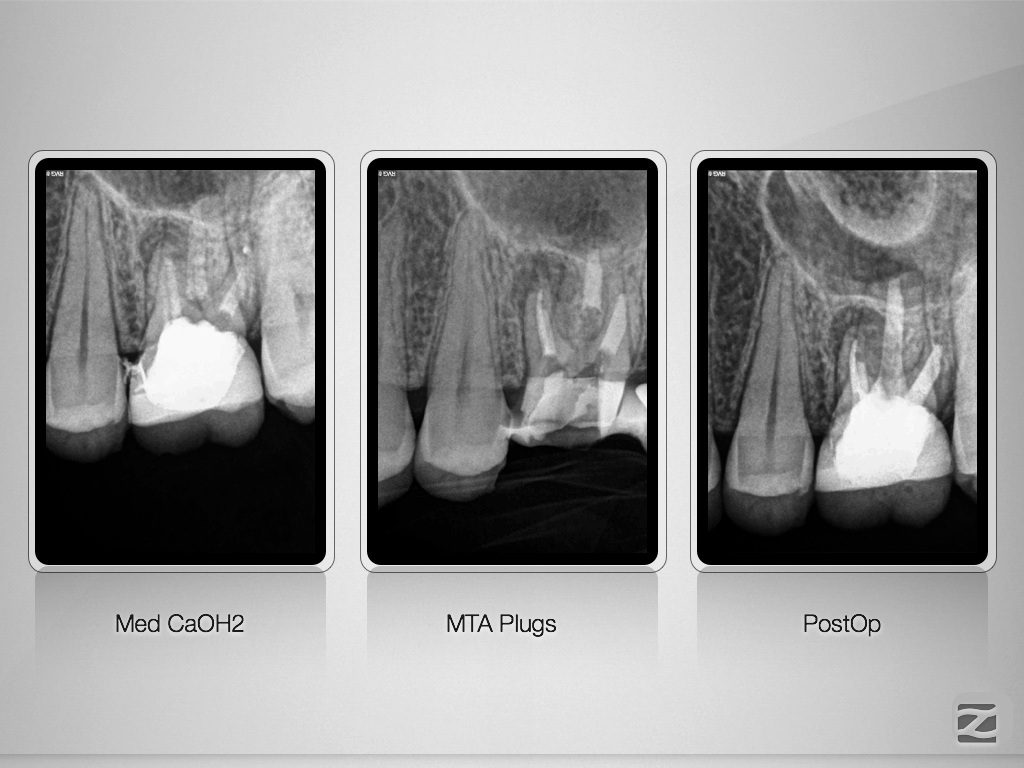

Revision nach Resektion